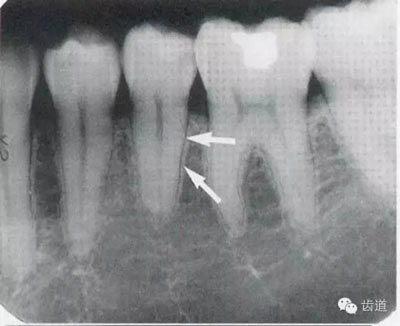

2)營(yíng)養(yǎng)管:

常見(jiàn)于下頜前牙區(qū),在牙根之間的牙槽骨內(nèi)并與牙長(zhǎng)軸平行的密度低的條狀影像。此為小血管進(jìn)入牙槽突的影像。